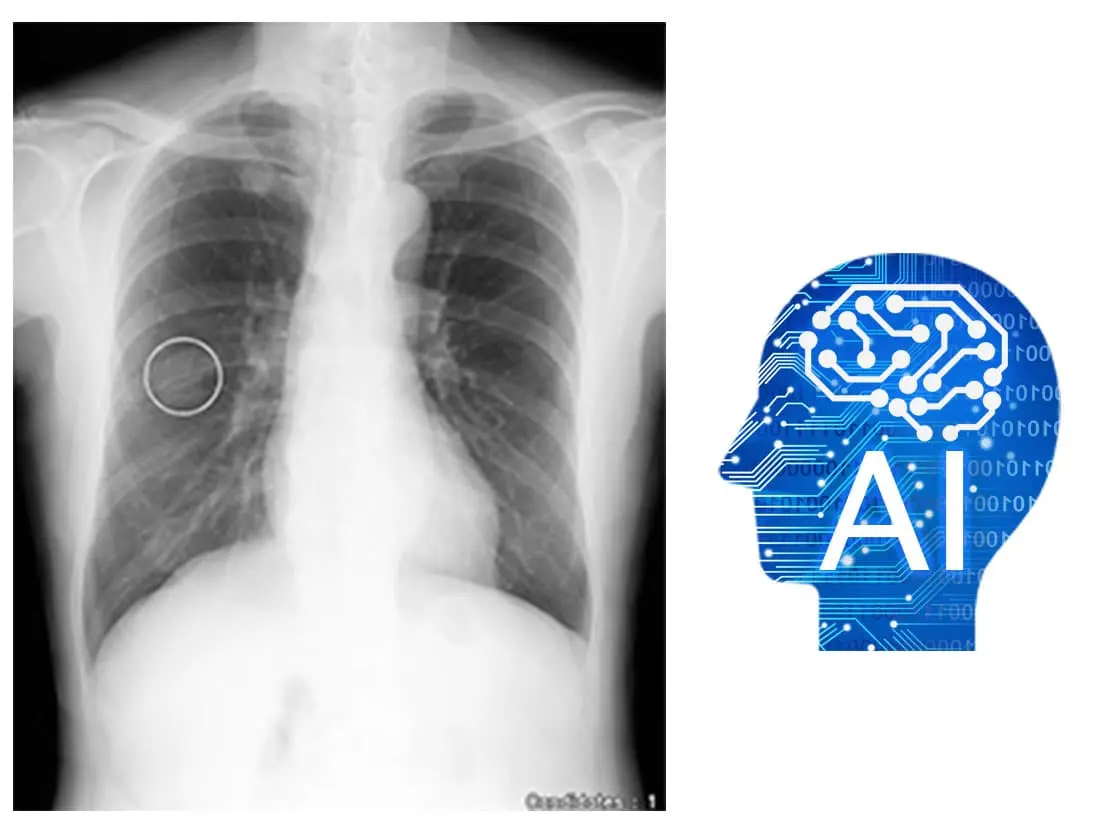

胸部AI解析と画像処理技術の併用により見落とし防止や確信度向上に貢献します。

胸部X線画像診断支援AI

胸部骨減弱処理「Bone Suppression処理」

胸部経時差分処理「Temporal Subtraction処理」

※CXR Finding-i は「画像診断⽀援ソフトウェア KDSS-CXR-AI-101(30300BZX00271000)」の呼称です。

※Bone Suppression / Temporal Subtractionは「画像診断ワークステーションImage Processing ProIP-Pro オプション(TS/BS)ソフトウェア(225ABBZX00123000)」の呼称です。